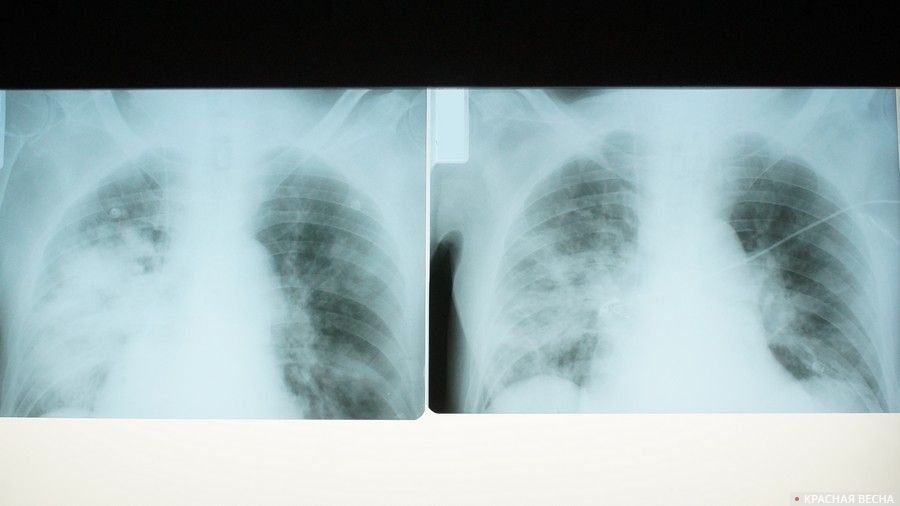

Пациенты больницы несколько раз в час надувают воздушные шары, лежа на спине. В ходе этого повышается давление в легких, что помогает расправить альвеолы и улучшает вентиляцию, подавляя развитие инфекции. Кроме дыхательной гимнастики комплекс упражнений включает в себя вибромассаж легких. Для этого врач отстукивает больных по спине.